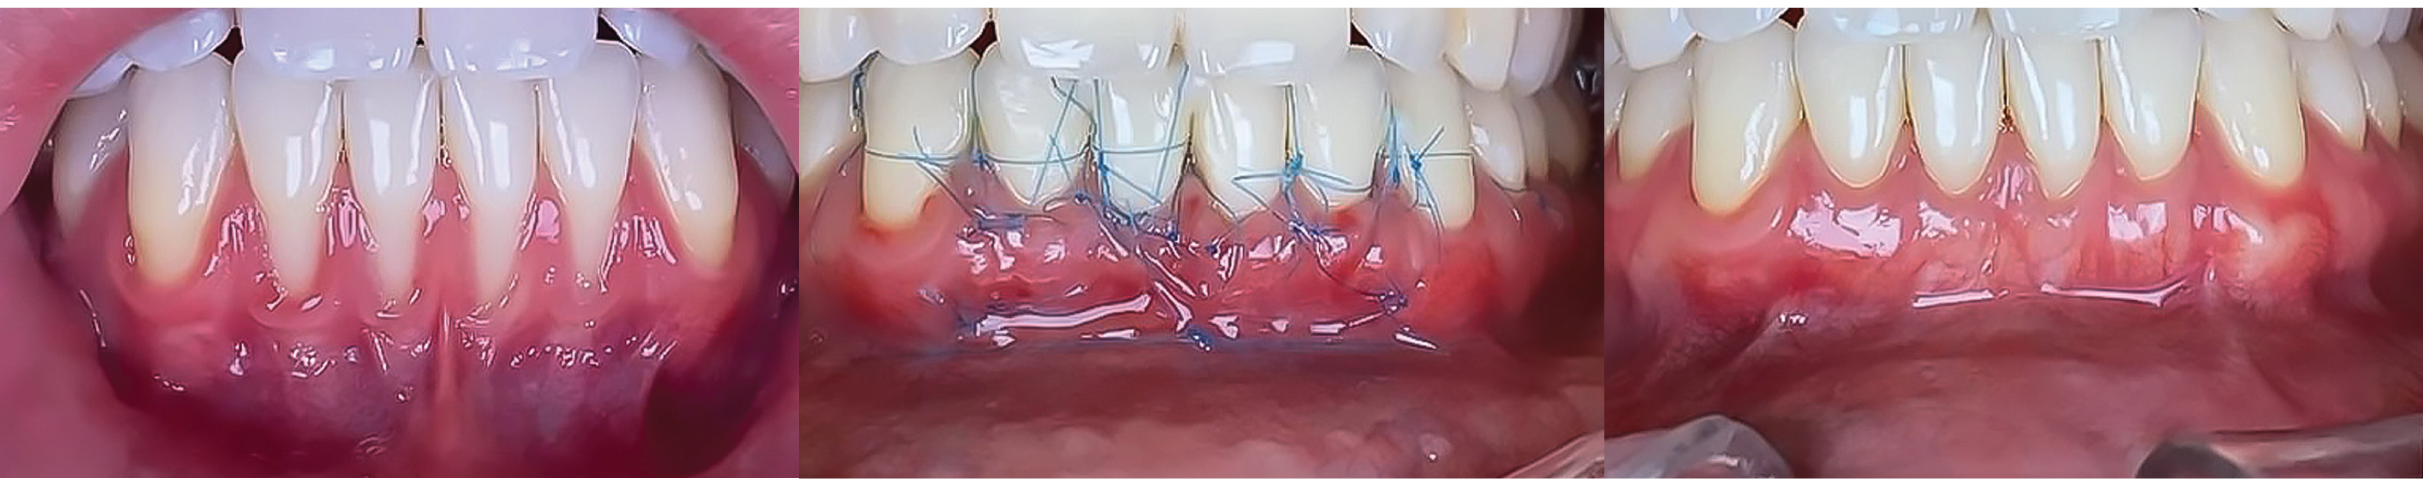

Soft tissue management and Tunnel Techniques. This two-day intensive course will provide participants with both theoretical foundations and practical experience in periodontal plastic surgery.

Through lectures, clinical case discussions, and hands-on practice, participants will learn advanced surgical techniques for root coverage, soft tissue grafting, and esthetic enhancement in periodontal procedures.

Soft tissue management and Tunnel Techniques. This two-day intensive course will provide participants with both theoretical foundations and practical experience in periodontal plastic surgery.

Through lectures, clinical case discussions, and hands-on practice, participants will learn advanced surgical techniques for root coverage, soft tissue grafting, and esthetic enhancement in periodontal procedures.

Coronally Advanced Flap for Multiple Recessions -Subepithelial Connective Tissue Graft |

The Laterally Closed Tunnel Technique |

Hands-OnLaterally Closed Tunnel and Coronary Advanced Flap for Multiple Recessions |

Coronally Advanced Flap for Multiple Recessions – Subepithelial Connective Tissue Graft

The Laterally Closed Tunnel Technique

Hands-On Laterally Closed Tunnel and Coronary Advanced Flap for Multiple Recessions